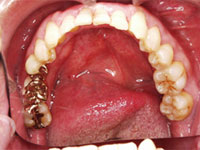

奥歯が1本もない状態のままで放置していた 患者様の事例

吉本歯科医院では、口内写真とパノラマレントゲンを撮影し、まずは顎の骨の状態まで詳しく確認しました。

口内写真.

院長の吉本の診断は以下でした。

1.奥歯がない状態で過ごしていた期間が長いため歯がない部分に隣の歯が倒れだして全体の歯並びを崩しはじめている

1. 接着ブリッジ

健康な歯を削る量を最大限に抑え、接着ブリッジを行なう